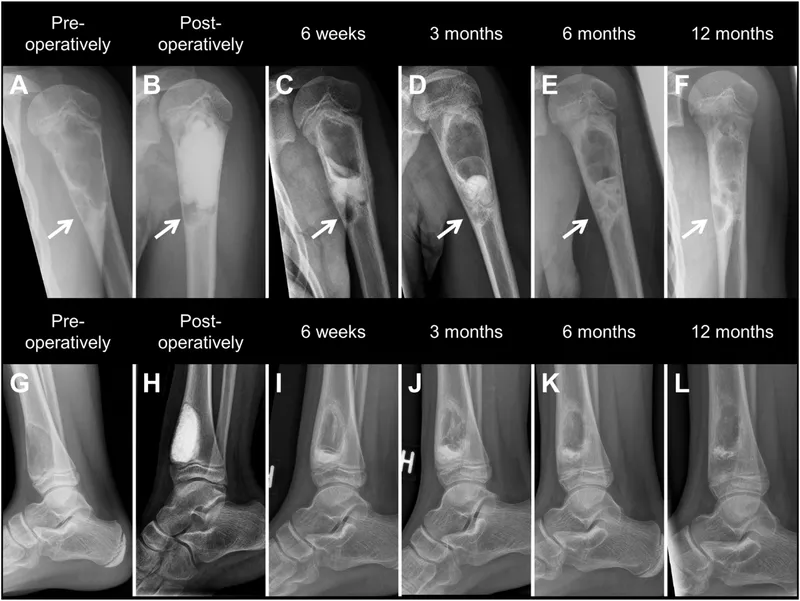

- X-ray: First line. Early: soft tissue swelling. Later (10-14 days): periosteal reaction, lytic areas. Chronic: sequestrum, involucrum.

| X-ray Hallmark | Periosteal reaction (late), lytic areas | Sequestrum, involucrum, cloaca |

- Pathophysiology: Sequestrum (necrotic bone), Involucrum (new periosteal bone), Cloaca (draining sinus). Brodie's abscess (chronic, localized).